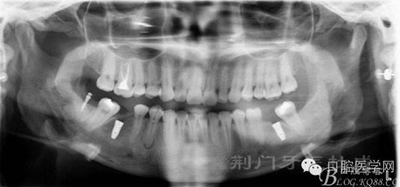

X線片

檢查:16齲壞穿髓,探(-)叩(+++),無松動,36 46 缺失,37 47 近中傾斜嚴(yán)重,44畸形中央尖牙體變色,叩(+),溫度測試無反應(yīng) ,18 28 38 48 萌出牙體偏頰

1:16 44根管治療后冠修復(fù),正畸牽引37 38 47 48,關(guān)閉36 46間隙后,拔除18 28

2:16 44根管治療后冠修復(fù),拔除18 28 38 48 后 36 46種植修復(fù) 37 47 遠中打種植支抗釘扶正37 47 后 種植修復(fù)冠